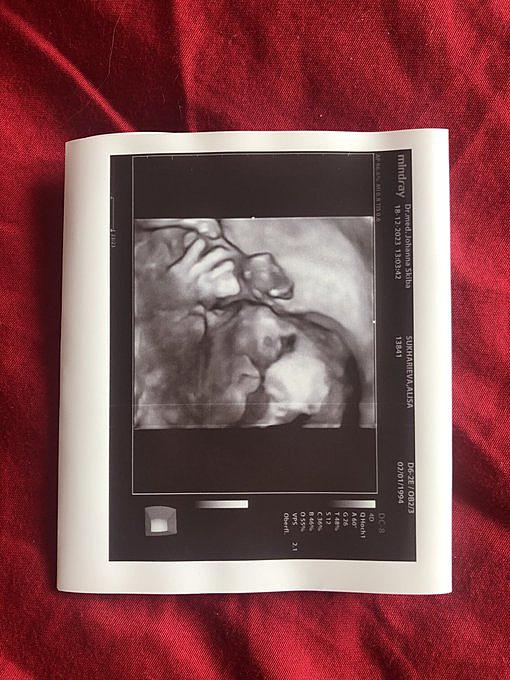

Эдвард ушёл в неактив

Украинский киберспортсмен Ioann “Edward” Sukharev решил приостановить свою карьеру и покинуть состав ESC Gaming CS 2. Он сообщил об этом своим подписчикам в социальных сетях.Украинский киберспортсмен Ioann “Edward” Sukharev решил приостановить свою карьеру и покинуть состав ESC Gaming CS 2.Причиной этого решения стало желание Сухарева больше времени проводить с семьёй. В ближайшем будущем он станет отцом, и для него важно не пропустить этот важный момент в жизни. Киберспортсмен признался, что CS всегда будет занимать особое место в его сердце, и поэтому он постарается найти время для трансляций своих игр на платформе Twitch. Вероятно, Сухарев больше не продолжит свою карьеру профессионального игрока.Он сообщил об этом своим подписчикам в социальных сетях.Сухарев присоединился к составу ESC Gaming в мае 2023 года. Вместе с командой он не достиг значительных результатов и участвовал в основном в небольших онлайн-турнирах.